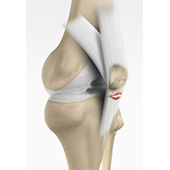

Patellar Tendon Rupture

The patellar tendon works together with the quadriceps muscle and the quadriceps tendon to allow your knee to straighten out. Patella tendon rupture is the rupture of the tendon that connects the patella (kneecap) to the top portion of the tibia (shinbone).